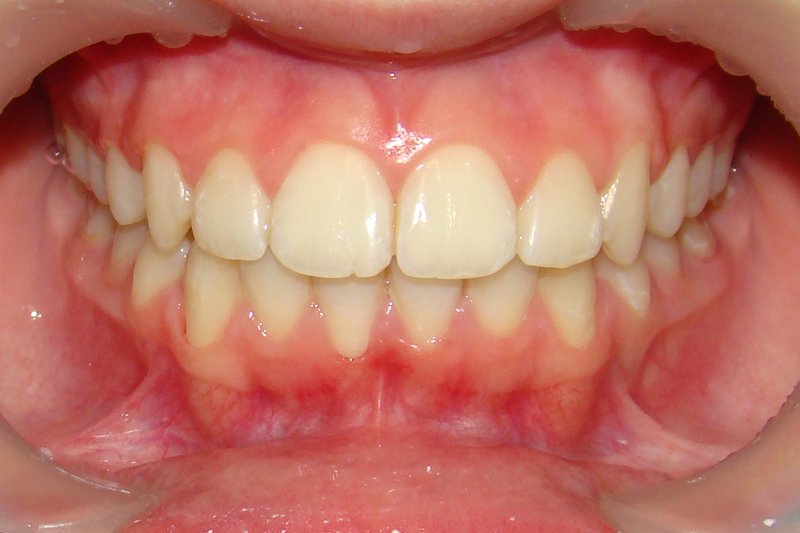

Покажу клинические случаи, чтобы было проще представить возможности ортодонтического лечения.

Это красиво!

Девушке 14 лет. Получилось все исправить без удаления зубов

А это уже молодой человек 10 лет. Тоже получилось справиться без удаления. Хоть оно и было показано. Но мальчик очень упорно носил специальные аппаратики и резиночки. Покажу со всех сторон. Этот случай победил в конкурсе на конференции

Девушке 11 лет. Я сильно настаивала на том, чтобы удалять зубы. Но решили попробовать без. Получилось